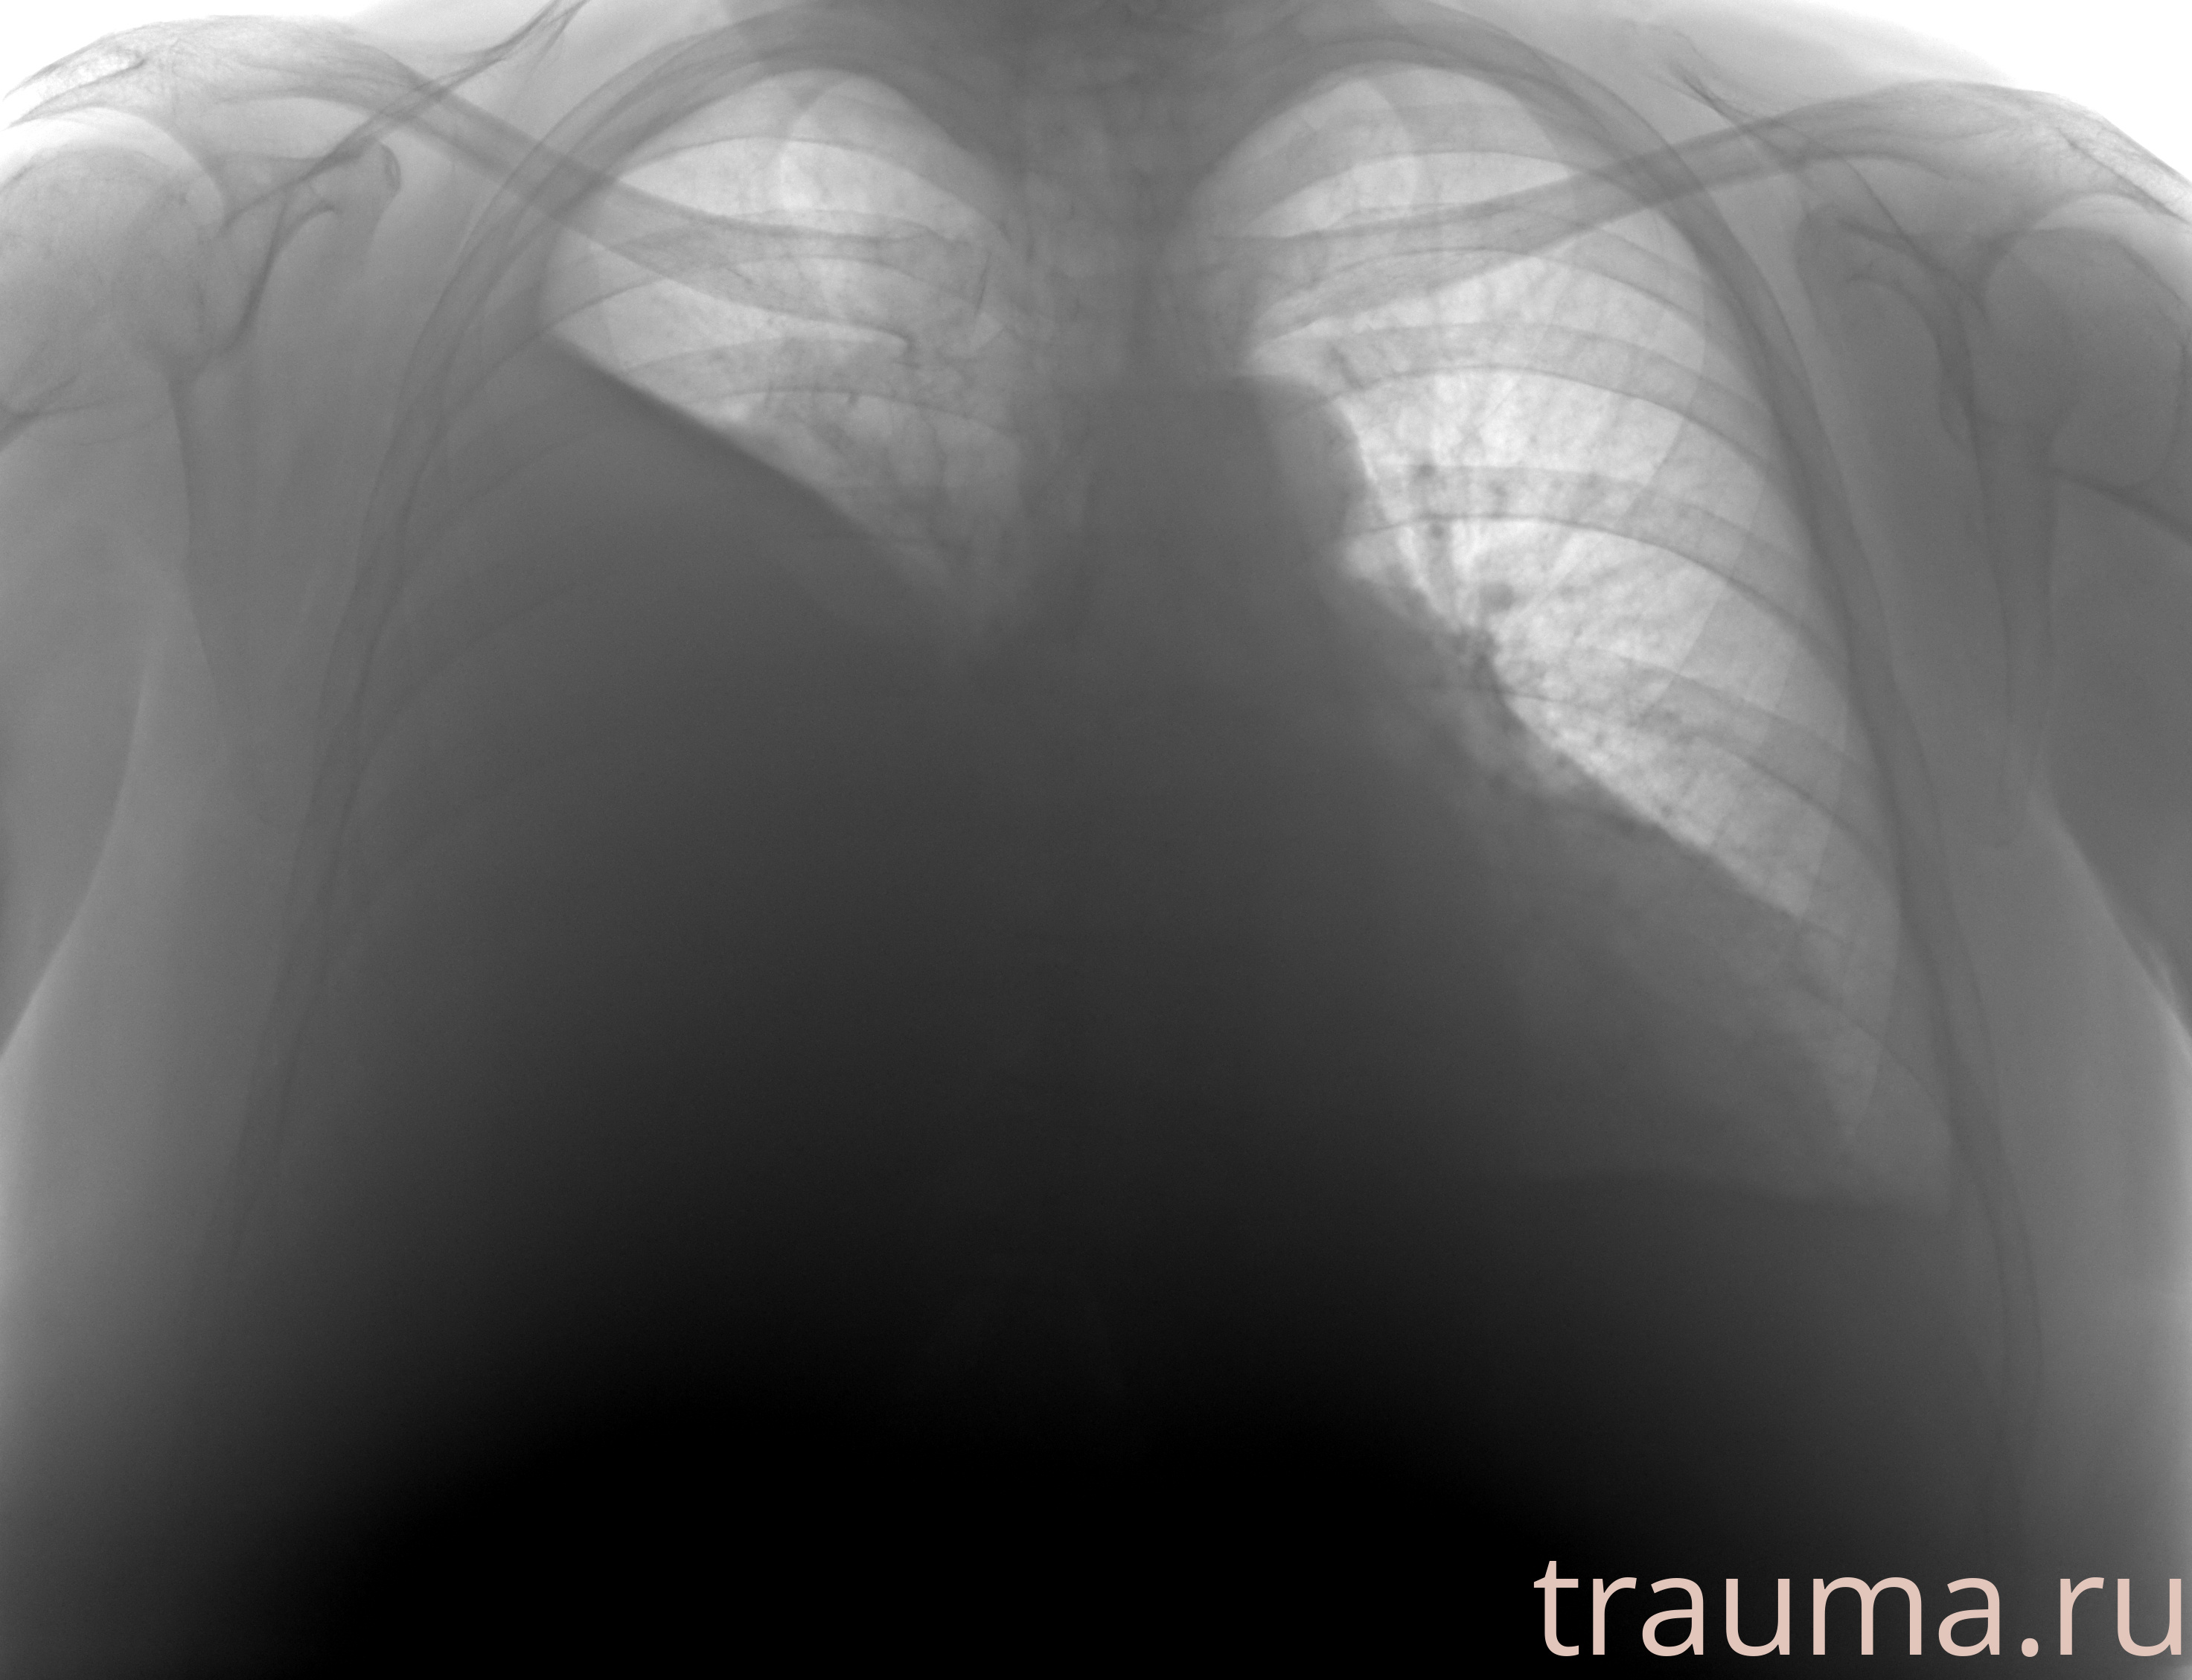

Рентгенограммы

Рентген на дому: по вашему адресу приезжает врач-рентгенолог, травматолог-ортопед с мобильным рентгеновским аппаратом, проводит диагностику травмы или заболевания, делает необходимые рентгенограммы, дает рекомендации по дальнейшему лечению. Получить качественные снимки в домашних условиях возможно благодаря уникальной методике, разработанной МосРентген Центром для института  Склифосовского

Яркость: 1   Контраст: 1   Инвертировать: 0 Увеличение: 1